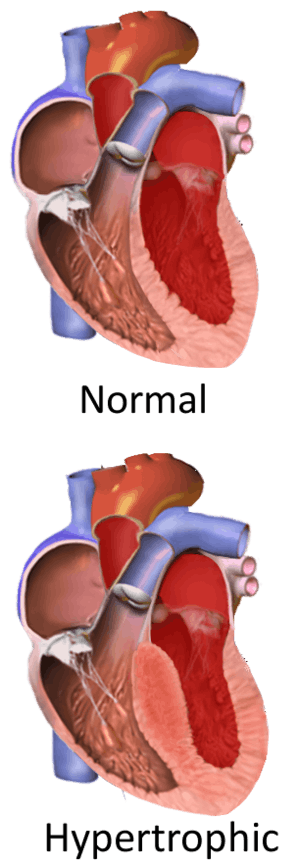

Individuals with HCM have some degree of left ventricular hypertrophy. Usually this is an asymmetric hypertrophy, involving the inter-ventricular septum, and is known as asymmetric septal hypertrophy.[15] This is in contrast to the concentric hypertrophy seen in aortic stenosis or hypertension. About two-thirds of individuals with HCM have asymmetric septal hypertrophy.

About 25% of individuals with HCM demonstrate an obstruction to the outflow of blood from the left ventricle during rest. In about 70% of patients, however, the obstruction can be provoked under certain conditions. This is known as dynamic outflow obstruction because the degree of obstruction is variable and is dependent on the loading conditions (ventricular filling and arterial blood pressure) and the contractility state of the left ventricle.